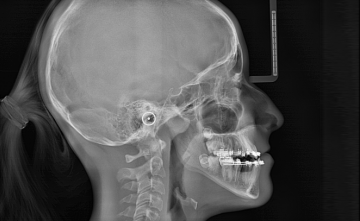

СТИЛЬНЫЙ И ЭФФЕКТИВНЫЙ

X-Mind® prime 3D Ceph сочетает в себе минималистичный и компактный дизайн с исключительной простотой использования. Новый цефалостат, специально разработанный для обеспечения максимального комфорта и стабильности пациента, и встроенная в ушной стержень интеллектуальная опорная плоскость Франкфурта, всегда обеспечивают быстрое и точное позиционирование пациента.

ПРЕВОСХОДНОЕ КАЧЕСТВО ИЗОБРАЖЕНИЯ

Использование современного цифрового датчика в сочетании с высокой производительностью программного обеспечения Acteon Imaging Suite обеспечивает превосходное качество изображения и непревзойденную надёжность при цефалометрии.

БЫСТРОЕ И ТОЧНОЕ СКАНИРОВАНИЕ ЦЕФАЛОМЕТРИИ

Выбор до 17 различных цефалометрических программ, включая высокоскоростное сканирование (всего 4,4 с) и новые режимы уменьшенного размера для обеспечения идеальной оценки интересующей области при минимальной дозе облучения.